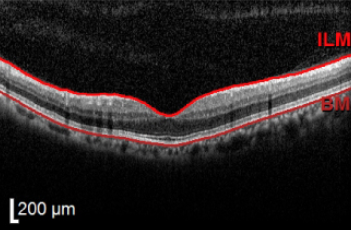

빛간섭단층촬영(OCT) 검사를 통해 황반 구조 변화를 정밀하게 확인할 수 있습니다 OCT 검사는 망막의 단면 구조를 확인할 수 있는 검사로 황반 부위의 두께 변화나 신생혈관 발생 여부를 확인하는 데 도움이 됩니다. 황반변성의 진단과 경과 관찰에 중요한 역할을 합니다.